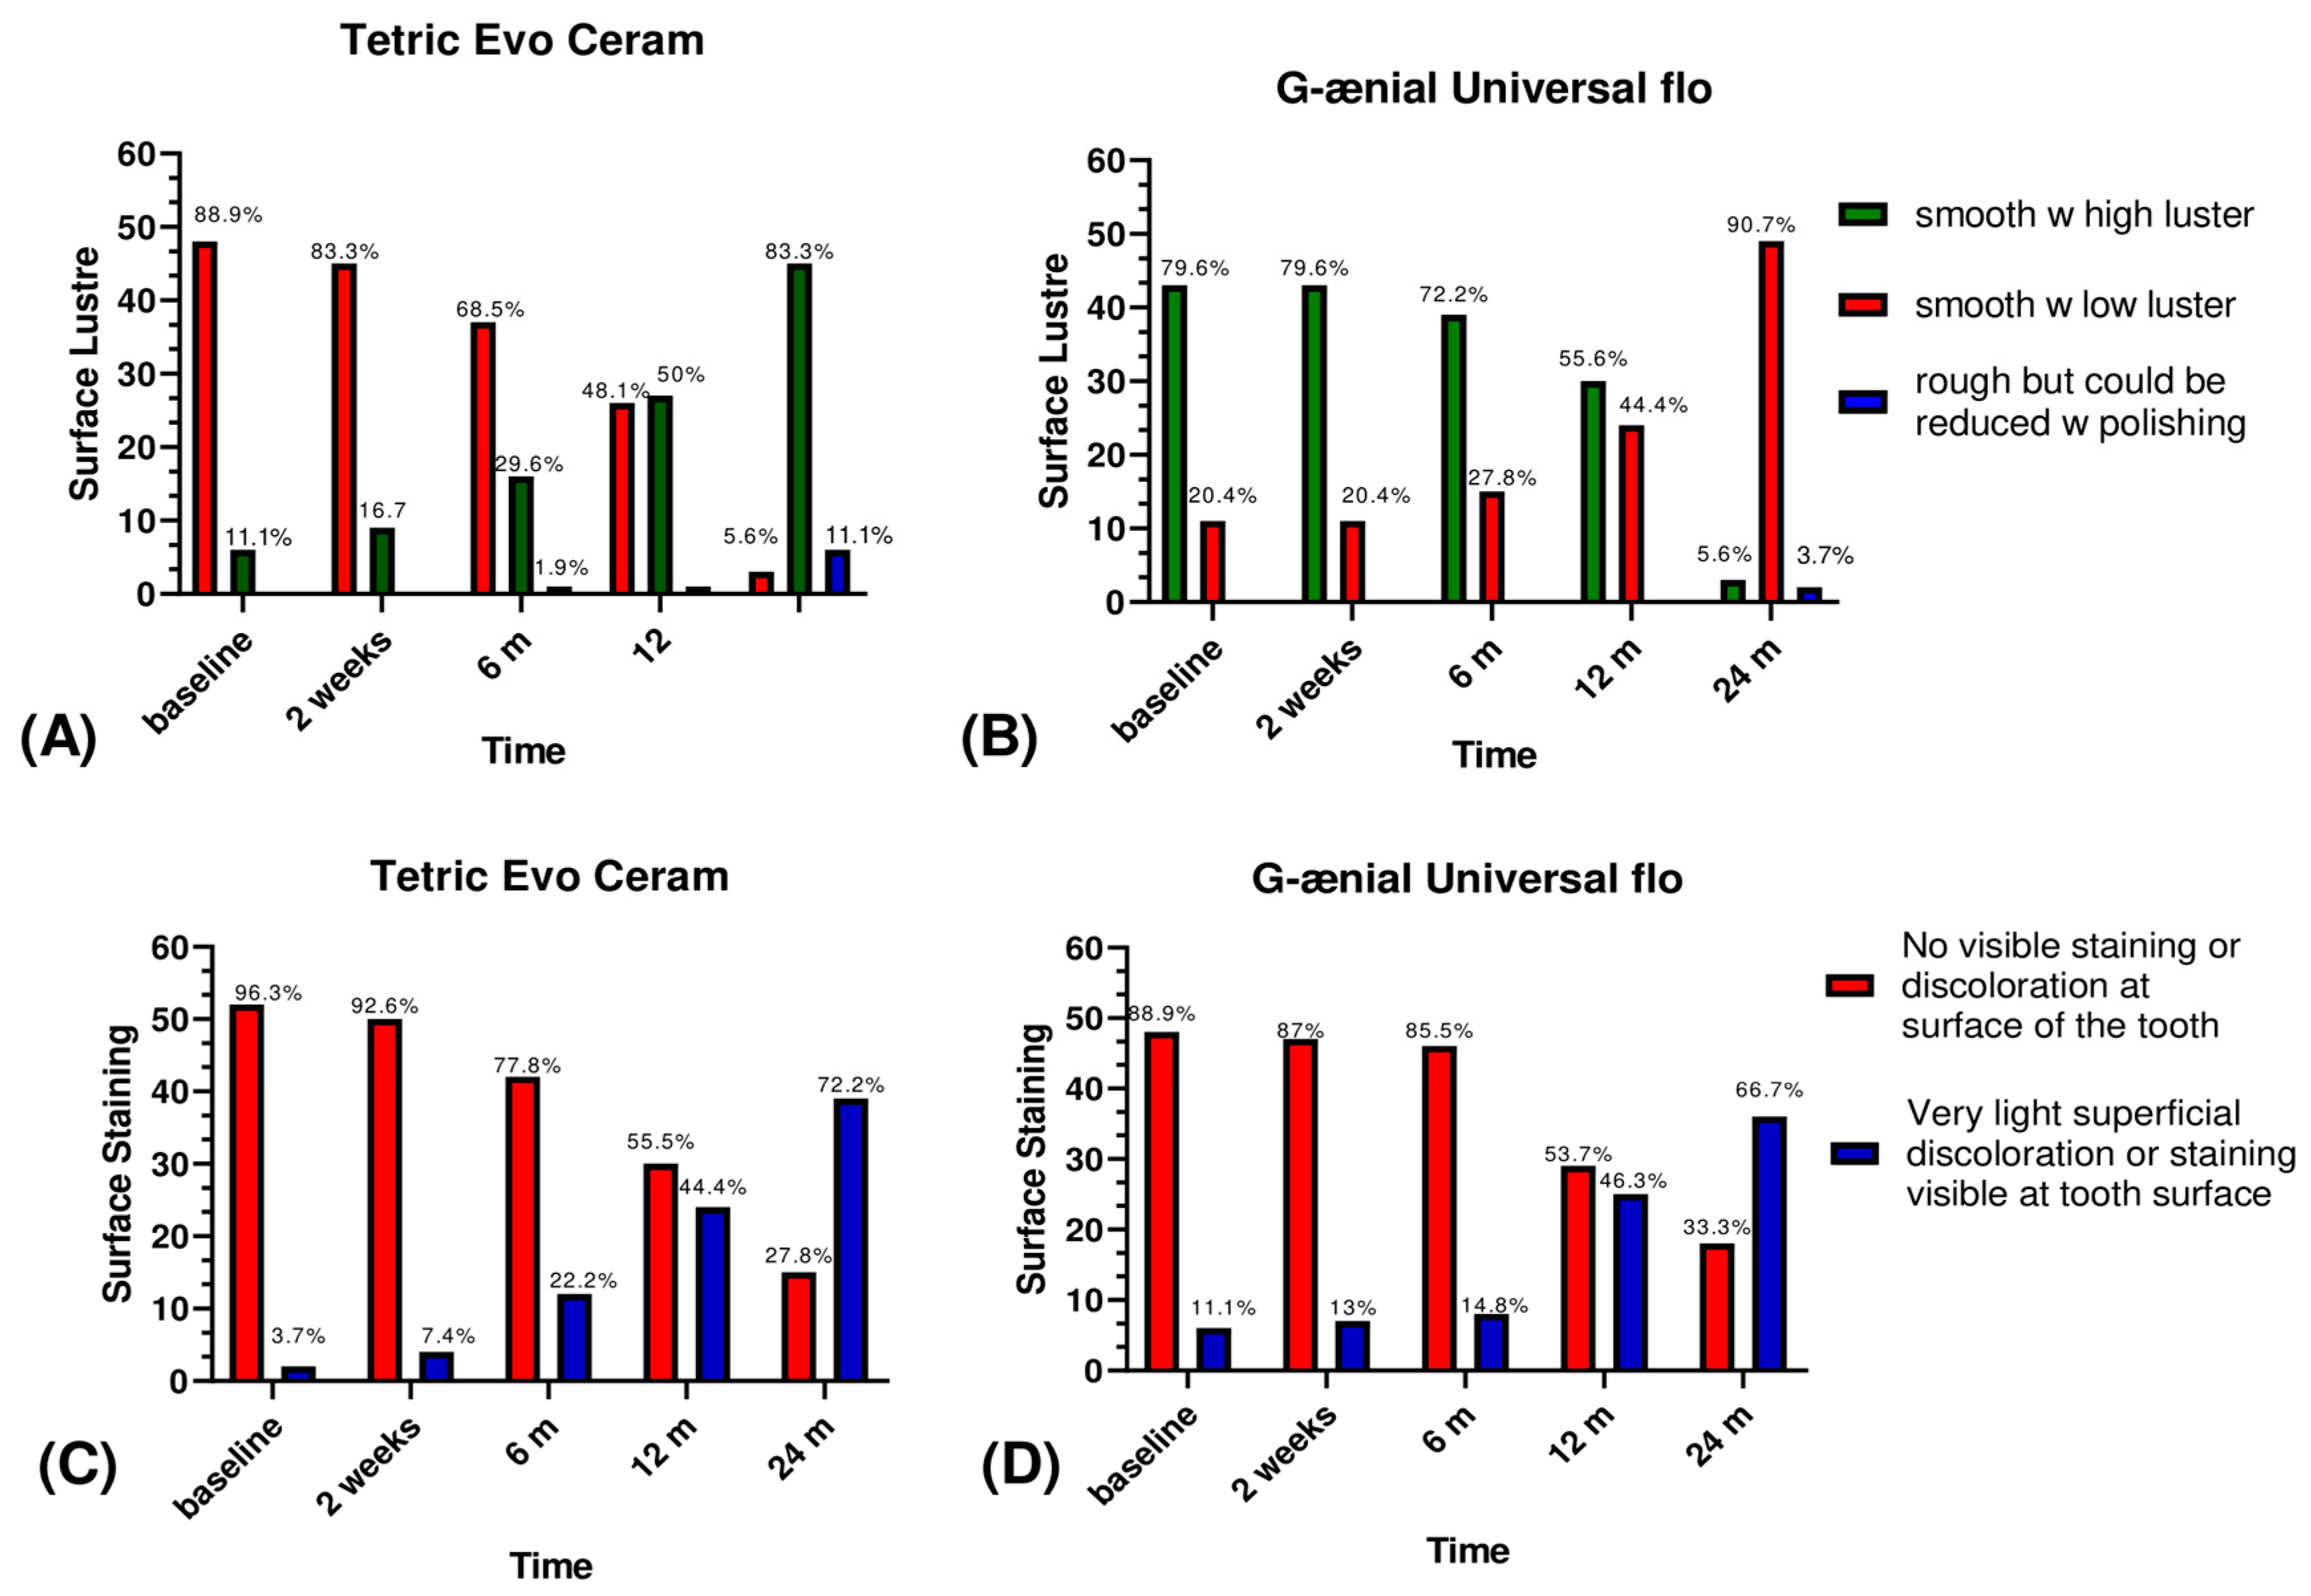

3.1. Esthetic Criteria

| Esthetic criteria | Surface luster | The surface of the filling is smooth with high luster | The surface of the filling is smooth but with a low luster | The surface of the filling is rough but could be reduced with a polishing | The surface of the filling is rough but could not be reduced with a polishing | The surface of the filling is severely rough with deep or irregular grooves | |

| Staining | Surface | No visible staining or discolouration at the surface of the tooth | Very light superficial discolouration or staining is visible at the tooth surface | Visible staining and discolouration at the tooth surface could be removed by polishing | Visible staining and discolouration at the tooth surface with deep penetration that could not be removed by polishing | Very deep surface discolouration | |